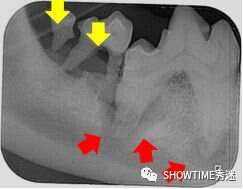

在它牙齿周围,用黄色箭头标识的是什么?

很遗憾,它不再只是牙结石,这里面是脓汁。

犬齿之间有软垢,包裹着牙齿,绿色圈内的就是未完全清理时的软垢。而我们发现,黄色框内的部分,犬齿之间的软组织大部分早已经在软垢的掩护下毫无踪迹。